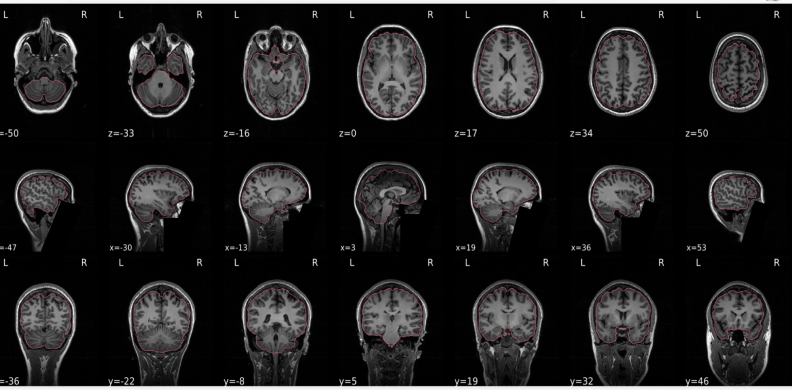

T1w skull stripping

Skull stripping is the process separating the brain (cortex and cerebellum) from the skull. The red line follows the outline of the brain and it separates it from the skull.

Example of a good subject

- There are no skull stripping errors, such as portions of the brain missing, or too much of the skull retained

- The red line follows the outline of the brain

Example of a bad subject

- There are skull stripping errors, such as portions of the brain missing, or too much of the skull retained

- NOTE: check all the images (slices) in the report. If only one image (slice) looks problematic, it is possible that the subject is okay and it is just a visual issue in that particular screenshot

Summary

| Good | Bad |

|---|---|

| The brain is fully inside the red line | Structures like the cranium or the eyes are inside the red line |

| No important brain structures are outside of the red line red line follows the natural outline of the brain | Important brain structures are missing inside of the red line |

-> if only one slice is problematic, it could be an issue related to the visual depiction of the data instead of an issue related to the test subject